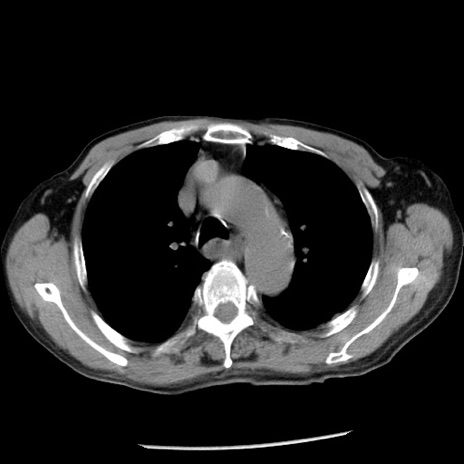

症例26(横断像)

【症例】80歳代男性

【主訴】嘔吐

【現病歴】昨晩2回嘔吐あり、今朝になっても嘔吐あり。来院。

【既往歴】胃潰瘍

【身体所見】意識清明、BT 37.6℃、BP 166/95mmHg、HR 100bpm、SpO2 97%、腹部:平坦・軟、腸蠕動音聴取良好、圧痛なし。

【データ】WBC 21900、CRP 1.46